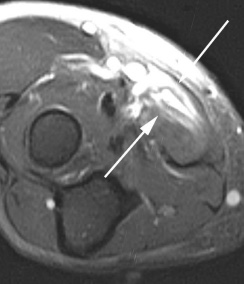

МРТ локтевого сустава. Т2-взвешенная МРТ, аксиальный срез ниже суставной щели. Разрыв двуглавой мышцы плеча (стрелка).

МРТ локтевого сустава. Т2-взвешенная аксиальная МРТ. Разрыв круглого пронатора (стрелка).